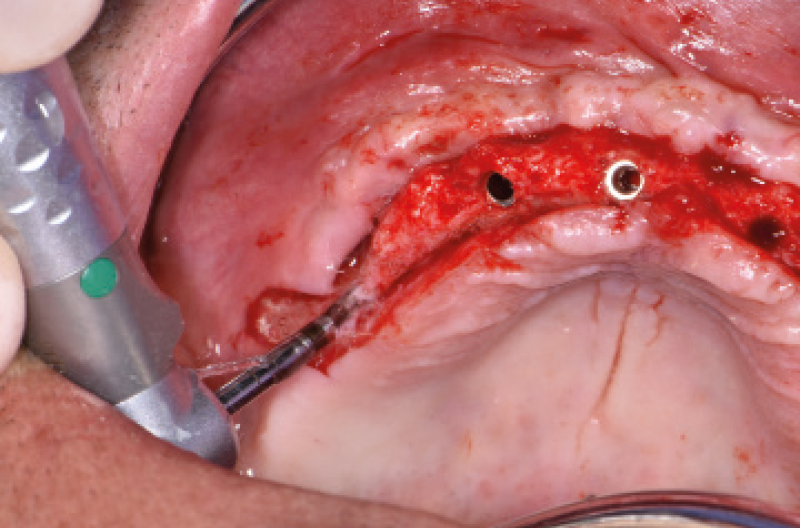

Nel mese di luglio 2019 il paziente ├© stato operato con il contestuale inserimento di 10 impianti, 4 nellŌĆÖarcata inferiore e 6 nellŌĆÖarcata superiore. Ho inserito 4 impianti Max Stability ├ś 3,75 mm nella zona della premaxilla, uno lungo 10 mm e gli altri tre da 12 mm di lunghezza; in regione 15 e 25 ho dovuto invece utilizzare delle frese da osseodensificazione per compattare lŌĆÖosso e traslare la parete mediale del seno mascellare per poter inserire 2 impianti Max Stability ├ś 3,75 L 12 mm inclinandoli lungo la parete stessa. Data la scarsa quantit├Ā e qualit├Ā di osso nel mascellare, ho rinunciato al carico immediato rinviando la procedura della protesizzazione immediata nella fase di riapertura degli impianti ad osteointegrazione avvenuta (Figg. 1-14).

Fig. 8 – Impianti frontali inseriti

Fig. 9 – Osseodensificazione e traslazione parete mediale del seno mascellare di destra

Fig. 10 – Impianto in regione 15 inclinato lungo la parete mediale del seno